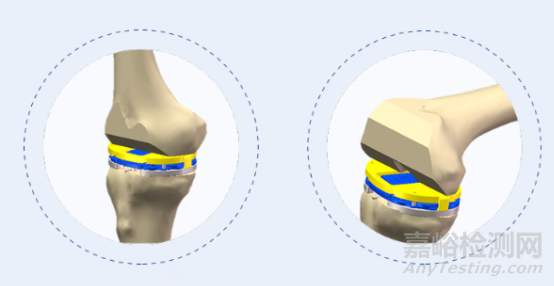

ARTHROBOT Keen

膝關(guān)節(jié)置換手術(shù)機(jī)器人系統(tǒng)“ARTHROBOT Keen”是由醫(yī)生與工科團(tuán)隊(duì)合作完成研發(fā)、具有完全自主知識(shí)產(chǎn)權(quán)的國產(chǎn)手術(shù)機(jī)器人。

該款機(jī)器人在術(shù)中可對(duì)膝關(guān)節(jié)活動(dòng)度、下肢對(duì)線與關(guān)節(jié)間隙進(jìn)行實(shí)時(shí)評(píng)估,依照術(shù)中實(shí)際情況實(shí)時(shí)調(diào)整規(guī)劃方案,并按規(guī)劃精準(zhǔn)完成股骨與脛骨側(cè)的截骨,誤差控制在1mm與1?范圍以內(nèi),實(shí)現(xiàn)膝關(guān)節(jié)個(gè)性化、精準(zhǔn)化手術(shù)治療。

2021年 6月9日,在完成近百例機(jī)器人輔助髖關(guān)節(jié)置換臨床實(shí)驗(yàn)手術(shù)的基礎(chǔ)上,鍵嘉又聯(lián)合醫(yī)院團(tuán)隊(duì)開展了機(jī)器人輔助全膝關(guān)節(jié)置換手術(shù)。